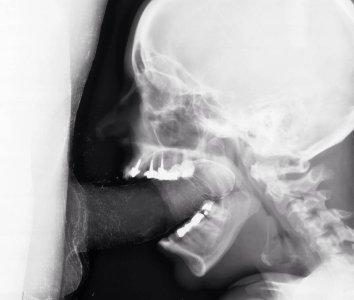

половой акт в разрезе, УЗИ, секс на рентгене

sex x-ray video

секс на томографе MRI

секс изнутри, половой акт в разрезе

как это снимал доктор Pek van Andel